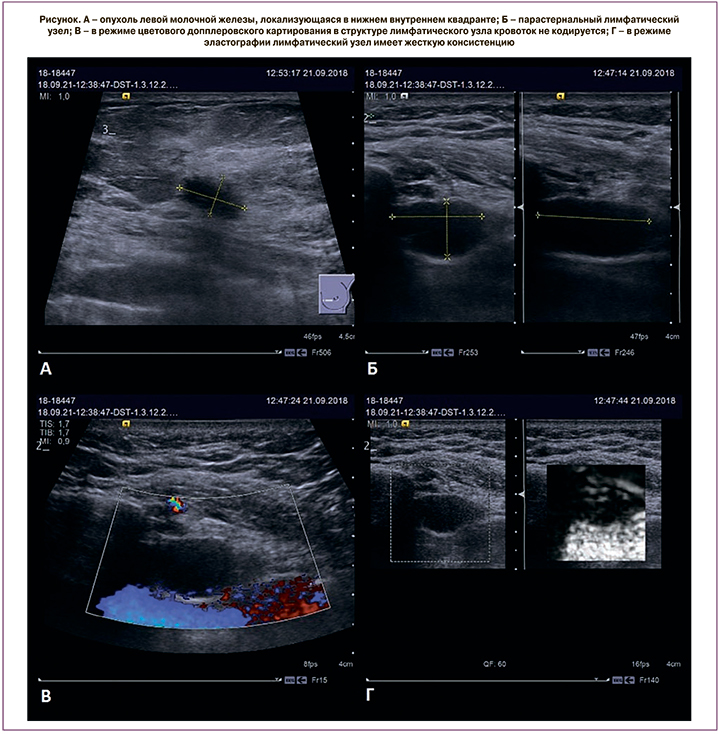

Пациентка, 59 лет. При поступлении в стационар жалоб не предъявляла. При проведении по месту жительства плановой маммографии молочных желез выявлено узловое образование левой молочной железы. Направлена в ФГБУ «НМИЦ Онкологии им. Н.Н. Блохина» для дообследования и определения тактики лечения. По данным маммографии, в нижнем внутреннем квадранте определяется гиперденсное образование неправильной формы с нечетким контуром 1,7×1,2×1,3 см, при УЗИ – гипоэхогенное узловое образование неправильной формы с нечеткими контурами 1,3×0,8×0,9 см. Злокачественных кальцинатов нет. В региональных зонах патологически измененных лимфатических узлов не выявлено. При пересмотре готовых гистологических препаратов № 18/34813: инвазивный рак НСТ G3 с выраженной лимфоидной инфильтрацией. Опухоль отрицательна по всем параметрам, по Ki67 – 80%. Тройной негативный рак. С целью дообследования пациентке дополнительно произведено УЗИ парастернальных лимфатических узлов. В парастеранальной области слева, во втором межреберье визуализируется гипоэхогенный лимфатический узел, округлой формы, размером 1,5×1,0×1,9 см, с ровным, четким контуром, структура не сохранена, корковый слой не дифференцируется, при эластографии – жесткой консистенции. В третьем межреберье визуализируется гипоэхогенный лимфатический узел, округлой формы, размером 1,5×1,5×0,9 см, с ровным, четким контуром, структура не сохранена, корковый слой не дифференцируется – жесткой консистенции (рисунок). Под ультразвуковой навигацией произведена тонкоигольная аспирационная биопсия описанных лимфатических узлов. Цитологическое заключение: в полученном материале найденные изменения соответствуют код: 8010/6 Рак, метастатический. Учитывая полученные данные, пациентке выставлена IIIA стадия, T1N2M0. Первым этапом планируется проведение химиотерапии с последующей секторальной мастэктомией и лучевой терапий на оставшуюся молочную железу с захватом парастернальной области.